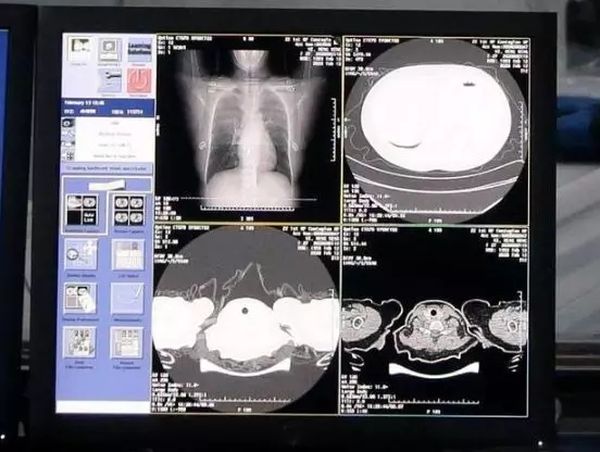

而阿里达摩院的AI算法,是基于当前最新的诊疗方案、钟南山等多个权威团队发表的关于新冠肺炎患者临床特征的论文,突破了训练数据不足的局限,基于5000多个病例的CT影像样本数据,学习训练样本的病灶纹理而研发建立的。

算法可将3-4小时的分析流程缩短到半小时,因此医生可以尽快掌握病毒是否有变异、以及特征,为防控、治疗提供更多依据。